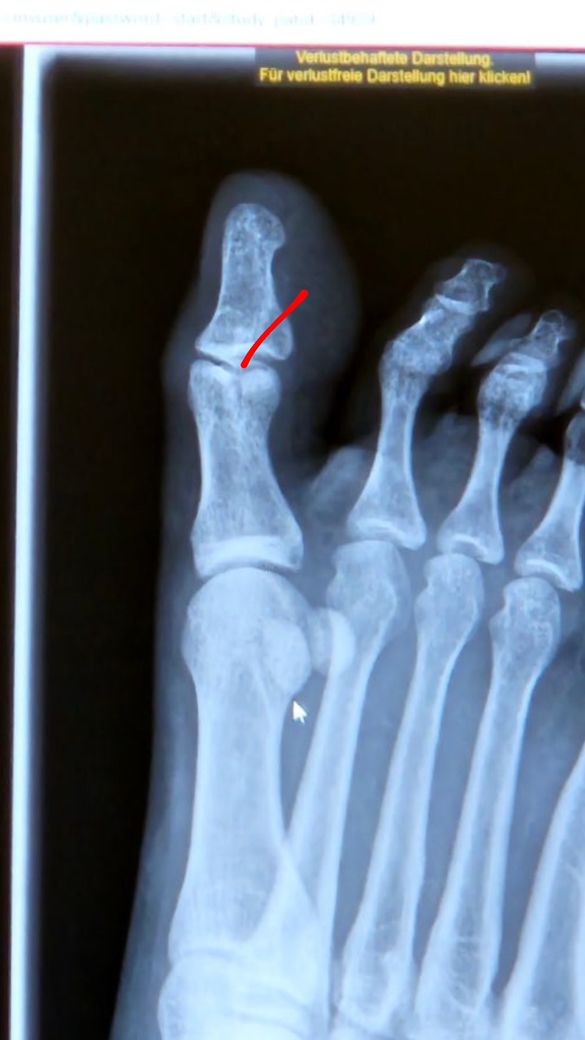

엄지발가락 골절 회복기간 얼마나 걸릴까요?

12월 23일에 다치고 12월 26일에 병원에 가서 골절 진단받고 반깁스를 시작했습니다. 1월 10일 병원을 다시 가보니 골절부위가 벌어졌다고 하셨는데 2주정도 더 지켜보겠다고 하셨습니다.

• 1번 째 사진